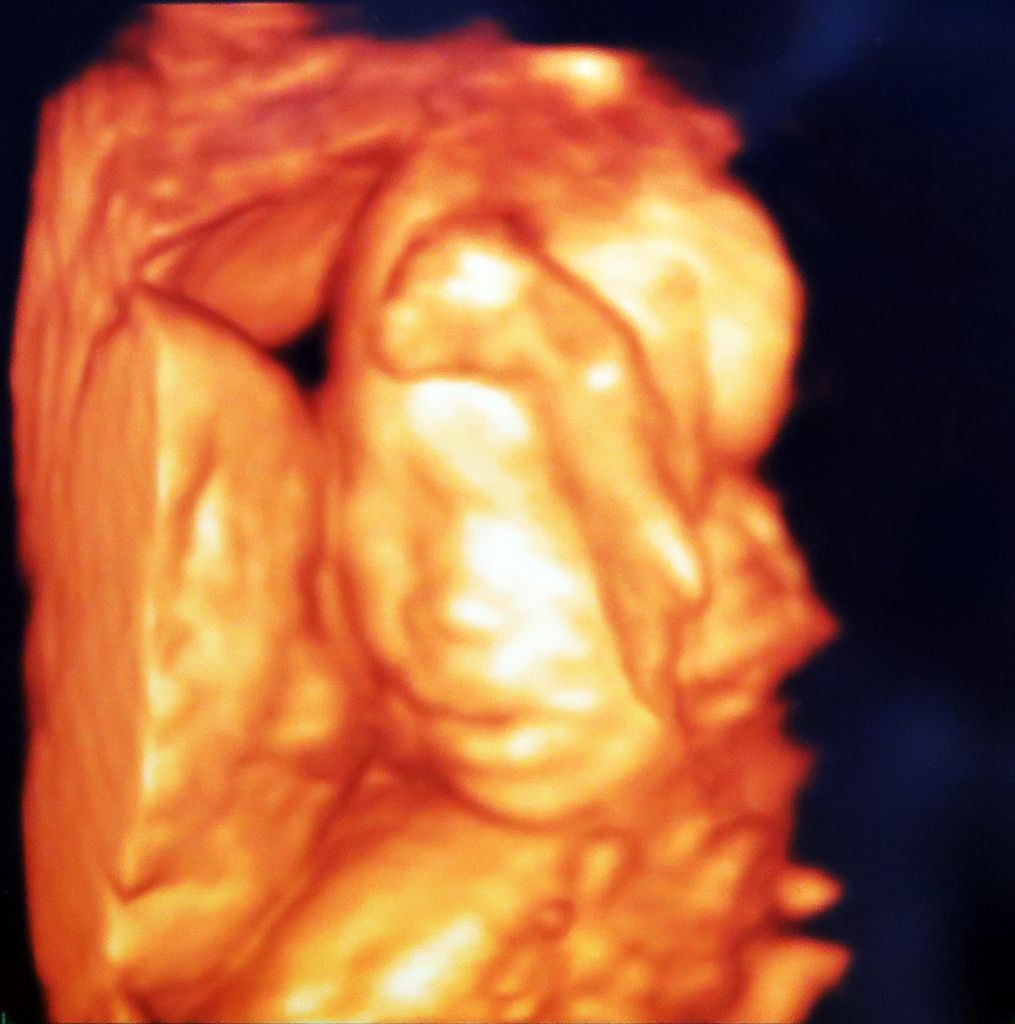

우리 가정에 기다리고 기다리던 새가족이 왔습니다^^ 2016년 10월 26일. 예정일을 지나서도 엄마 뱃속이 좋다며 나오지 않으려는 별이. 의사 선생님과 상담하여 유도분만을 시도하기로 한 날이되어 아침부터 병원으로 향했습니다. 촉진제를 맞고 얼마 되지 않아 진통이 시작되었습니다. 진통하는 동안 수시로 태동검사를 하더라구요. 진통과 분만에 도움이 된다하여 틈틈이 짐볼을 가지고 운동했어요. 부모와 할머니 할아버지들의Read More →